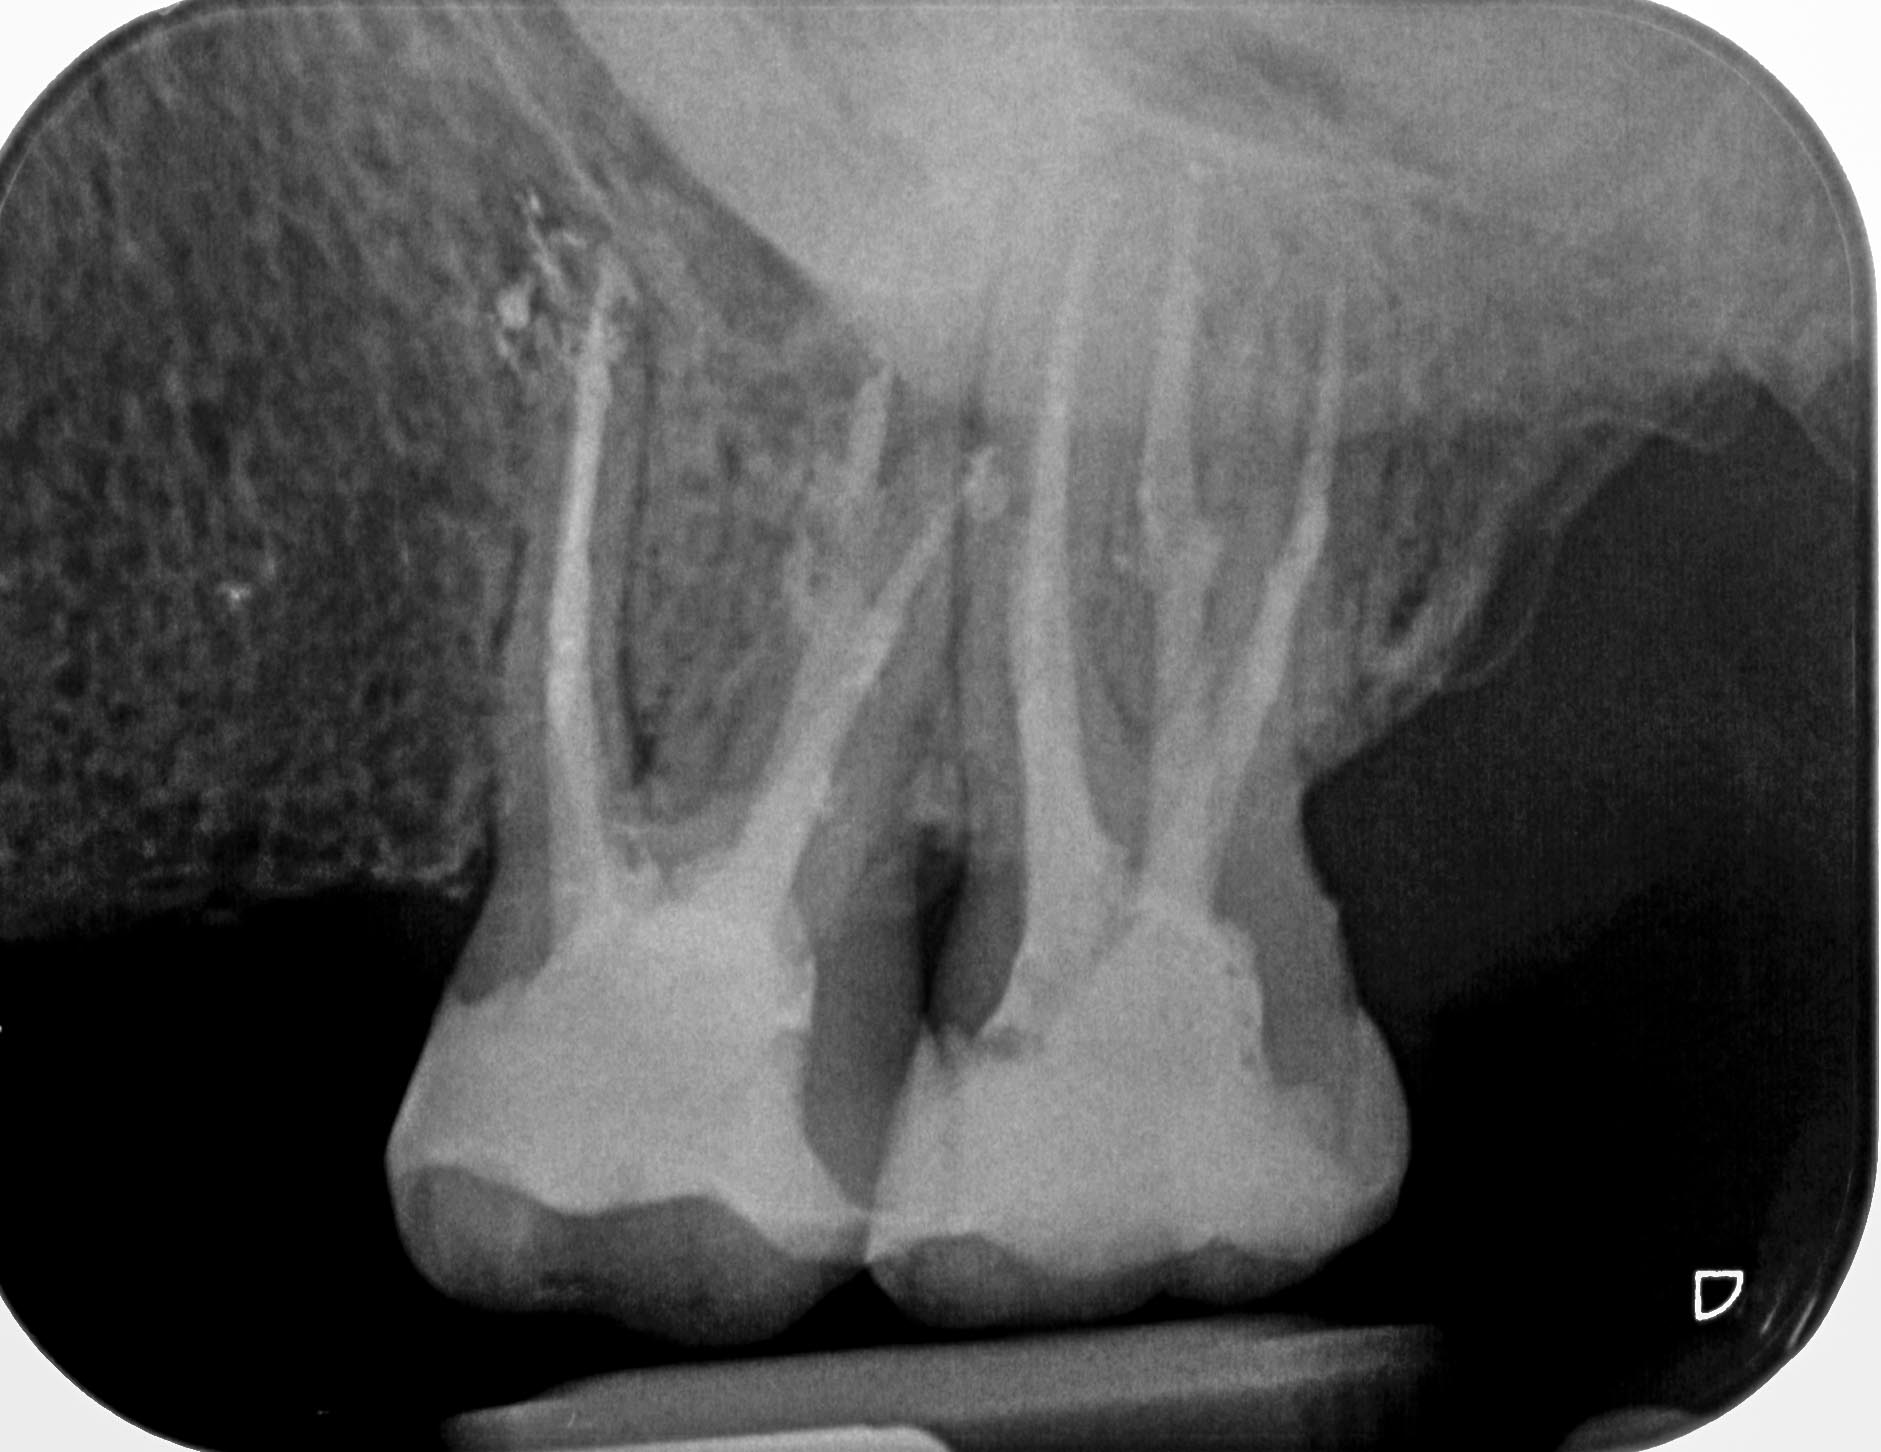

BN2627_1a-1-9 Veröffentlicht 1. Dezember 2014 am 1881 × 1452 in Unerwartete Anatomie Zahn 26, 27- die WF